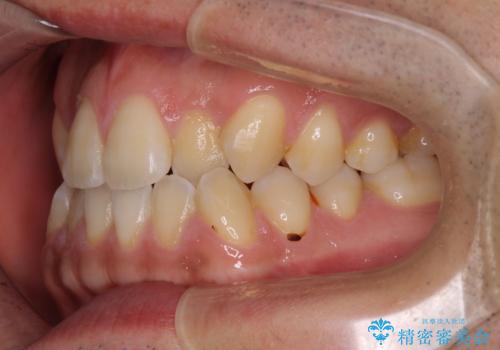

- 前歯のデコボコを気にして来院された患者様です。

歯列としてはワイヤー装置でもインビザラインでも対応可能でしたが、インビザラインが苦手とする上顎側切歯(真ん中から2番目の歯)の舌側転位が顕著でした。

治療の確実性を上げるために、インビザライン開始前に上顎のワイヤー装置にて舌側転位を解消し、その後インビザラインにて矯正治療を行うこととしました。

前歯のデコボコが早めに改善され、スムーズに治療を終えることができました。